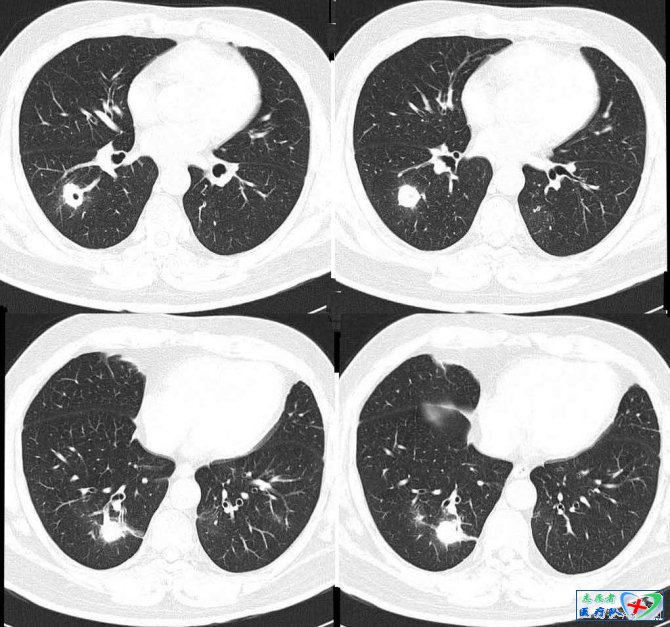

7、蜂窝征:

在纵隔窗下观察可见由多个小泡集成蜂窝状,其大小比较一致,以浅淡实变为主,此征仅见于肺泡癌。病理上为癌细胞沿肺泡壁生长,肺结构无破坏,未封闭肺泡腔,由于腔内遗留粘液加之以细支气管被肿瘤浸润形成的活瓣样阻塞导致管腔不同程度的扩张。